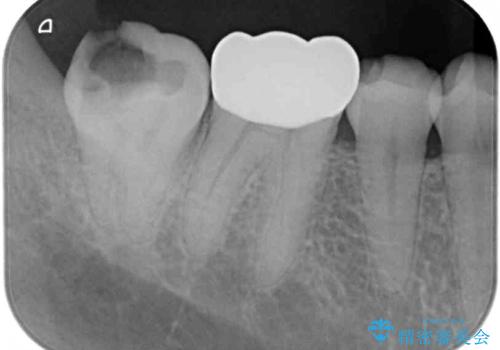

レントゲン写真から、神経の近くにまでむし歯が及んでいる様子が分かり、範囲も広範囲であったので、まずは仮歯に置き換え、その後オールセラミッククラウンにて補綴治療を行うこととしました。

処置を開始するに当たり検査診断を行ったところ、歯髄組織にまでむし歯が及んでいる可能性が示唆されたため、万が一の事態に備えてラバーダム装着による無菌的環境にて虫歯除去を行うこととしました。

虫歯は歯髄組織のギリギリにまで及んでいたものの、歯髄組織が露出することはなく、処置から数日経った日に行った検査でも歯髄組織の異常所見は認めれらませんでした。